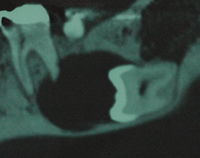

全身麻酔下で、腫瘍と一緒に下顎を切除しました。

切除後は腰の骨(腸骨)を移植し、顎を再建しました。

※写真をクリックすると大きい画像が開きます。